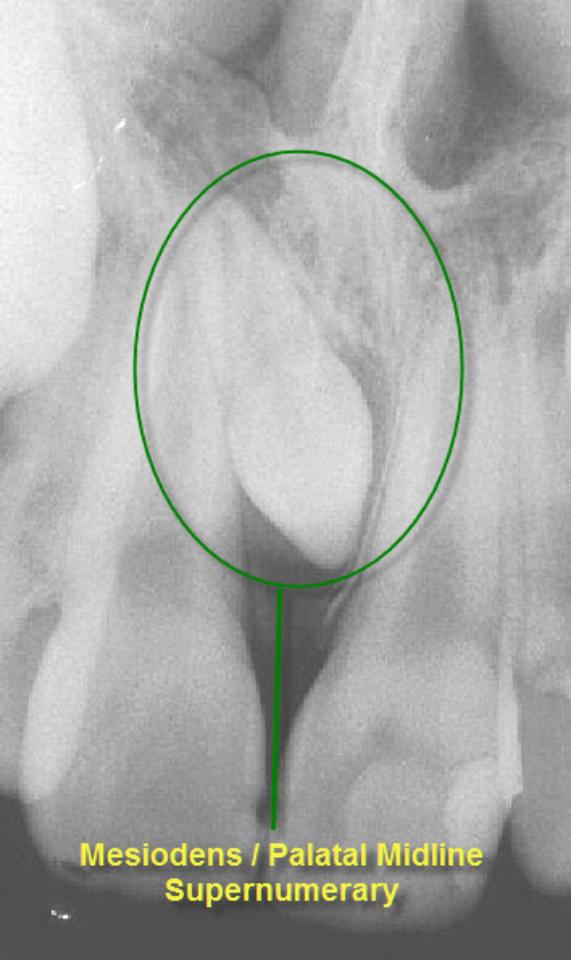

The prevalence of supernumerary teeth is reportedly between 0.15 – 3.9%. Most commonly, extra teeth are found between the upper central incisors (mesiodentes) or in the region of the premolars (paramolars) or very occasionally, behind the wisdom teeth (distomolars).

80 – 90% of all supernumerary teeth occur in the upper jaw. Half are found at the ‘front’ of the upper jaw. Mesiodentes frequently interfere with the eruption and alignment of the upper incisors. They can delay or prevent eruption, displace or rotate the erupting central incisors or less commonly, ‘bend’ (dilaceration) the developing roots of the central incisors so that tooth eruption is slowed / stopped, ‘eat away’ (resorption) the surrounding teeth, develop cysts around the crowns of the extra teeth (dentigerous cyst formation) and loss of tooth vitality. Rarely, the mesiodens can erupt into the nasal cavity